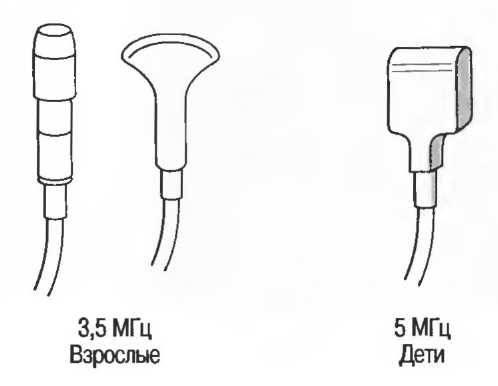

Затухание

Ткани тела поглощают и рассеивают ультразвук по-разному. Высокие частоты поглощаются и рассеиваются (гасятся) в большей степени, чем низкие. Поэтому, чтобы достичь более глубоких тканей, необходимо использовать более низкие частоты, так как менее вероятно, что эти волны затеряются при прохонодении через ткани. На практике оптимально использовать частоту около 3,5 МГц для глубокого сканирования у взрослых и частоту 5 МГц и выше для исследования более худых пациентов или детей. Частота 5 МГц и выше используется для исследования поверхностных органов у взрослых.

Высокие частоты дают более детальное изображение, но имеют меньшую проникающую способность.

Выбор соответствующего датчика

Наилучшим датчиком для общей практики является конвексный датчик с частотой 3,5 МГц с фокусировкой на расстоянии 7-9 см. Если такого датчика нет, необходимо наличие линейного секторного датчика с частотой 3,5 МГц. При необходимости исследования детей и худых взрослых желательно дополнить набор датчиком с частотой 5 МГц с фокусировкой 5-7 см.

1. Ультразвуковые исследования в акушерстве. Для общих исследований в акушерстве используется линейный или конвексный датчик с частотой 3,5 или 5 МГц с глубиной фокусировки на 7-9 см. Если закупается только один датчик, выбирайте датчик с частотой 3,5 МГц. Датчик с частотой 5 МГц предпочтителен на ранних сроках беременности. В поздние сроки беременности лучше использовать датчик с частотой 3,5 МГц.

2. Ультразвуковые исследования в общей практике. Если проводятся исследования в верхней части живота и таза у взрослых, в том числе и акушерские исследования, предпочтительнее выбор секторного или конвексного датчиков с частотой 3,5 МГц с глубиной фокусировки на 7-9 см.

3. Ультразвуковые исследования в педиатрии. Для детей необходим датчик с частотой 5 МГц с глубиной фокусировки на 5-7 см. При исследовании мозга новорожденного используется секторный датчик с частотой 7,5 МГц с глубиной фокусировки на 4-5 см (этот датчик также используется для исследования яичек и структур шеи у взрослых).